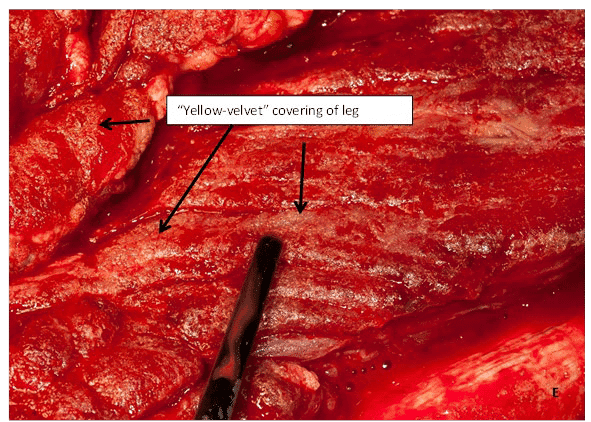

(E) Придивившись до рани, можна побачити «жовто-оксамитове» покриття. Це вказує на інфекцію Aspergillus.